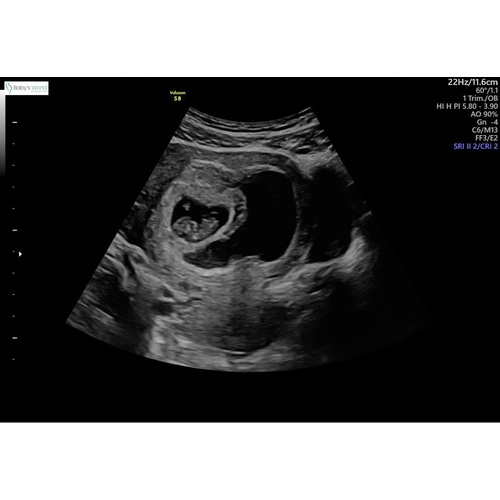

De echoscopiste van de “pretecho” (was heel lief door m’n vriend ingepland, zodat ik een keer rustig naar de baby kon kijken, zonder alle hectiek en doemscenario’s eromheen) heeft uitgelegd dat m’n lichaam de lege vruchtzak kwijt wil, wat dus het bloedverlies veroorzaakt, maar dat er een grote kans bestaat dat deze tzt opgenomen wordt door m’n lichaam. Met de baby gaat het goed. Is heel stoer uitgegroeid naar een embryo van ruim 2 cm en vandaag heb ik hem/haar zien bewegen op de echo. Toen viel er echt even een last van m’n schouders. De baby lag er, in mijn ogen, zeer tevreden bij en lag lekker te bewegen. Bij elke onverklaarbare steek of wat heviger bloedverlies gaat er toch van alles door je heen. Fijn om dan even te kunnen zien dat hij/zij het toch goed maakt en zich goed ontwikkeld.